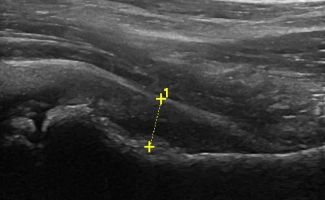

Το Υπερηχογράφημα Ισχίου μπορεί να διαγνώσει μία σειρά παθολογιών και κακώσεων στην άρθρωση, τους τένοντες, τους θυλάκους και τα νεύρα της περιοχής του ισχίου, όπως:

- Συλλογή υγρού